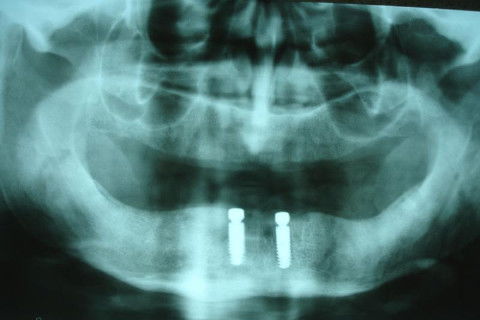

RX Panorâmico para exodontias e instalação de implantes imediatos na região entre os forames mentuais.

Após exodontia, instalação dos implantes imediatos e abutments magnéticos. Cirurgia realizada por Dr. Angelo Menuci Neto.